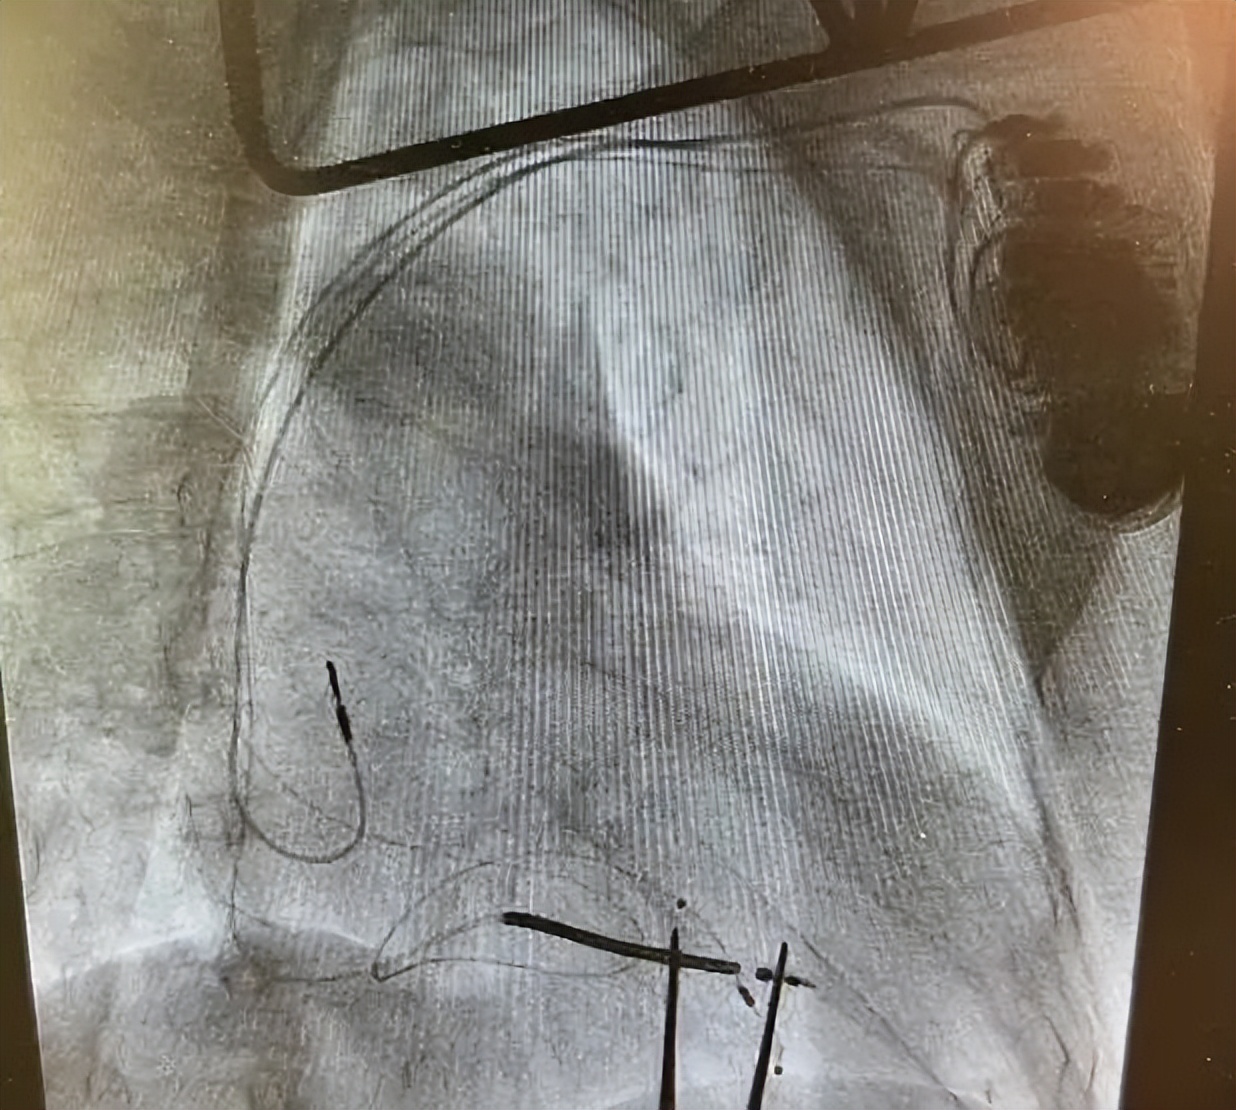

冠脉静脉造影

术中,成功将三个电极植入到右心房、右心室、左心室(冠状静脉分支远端)。